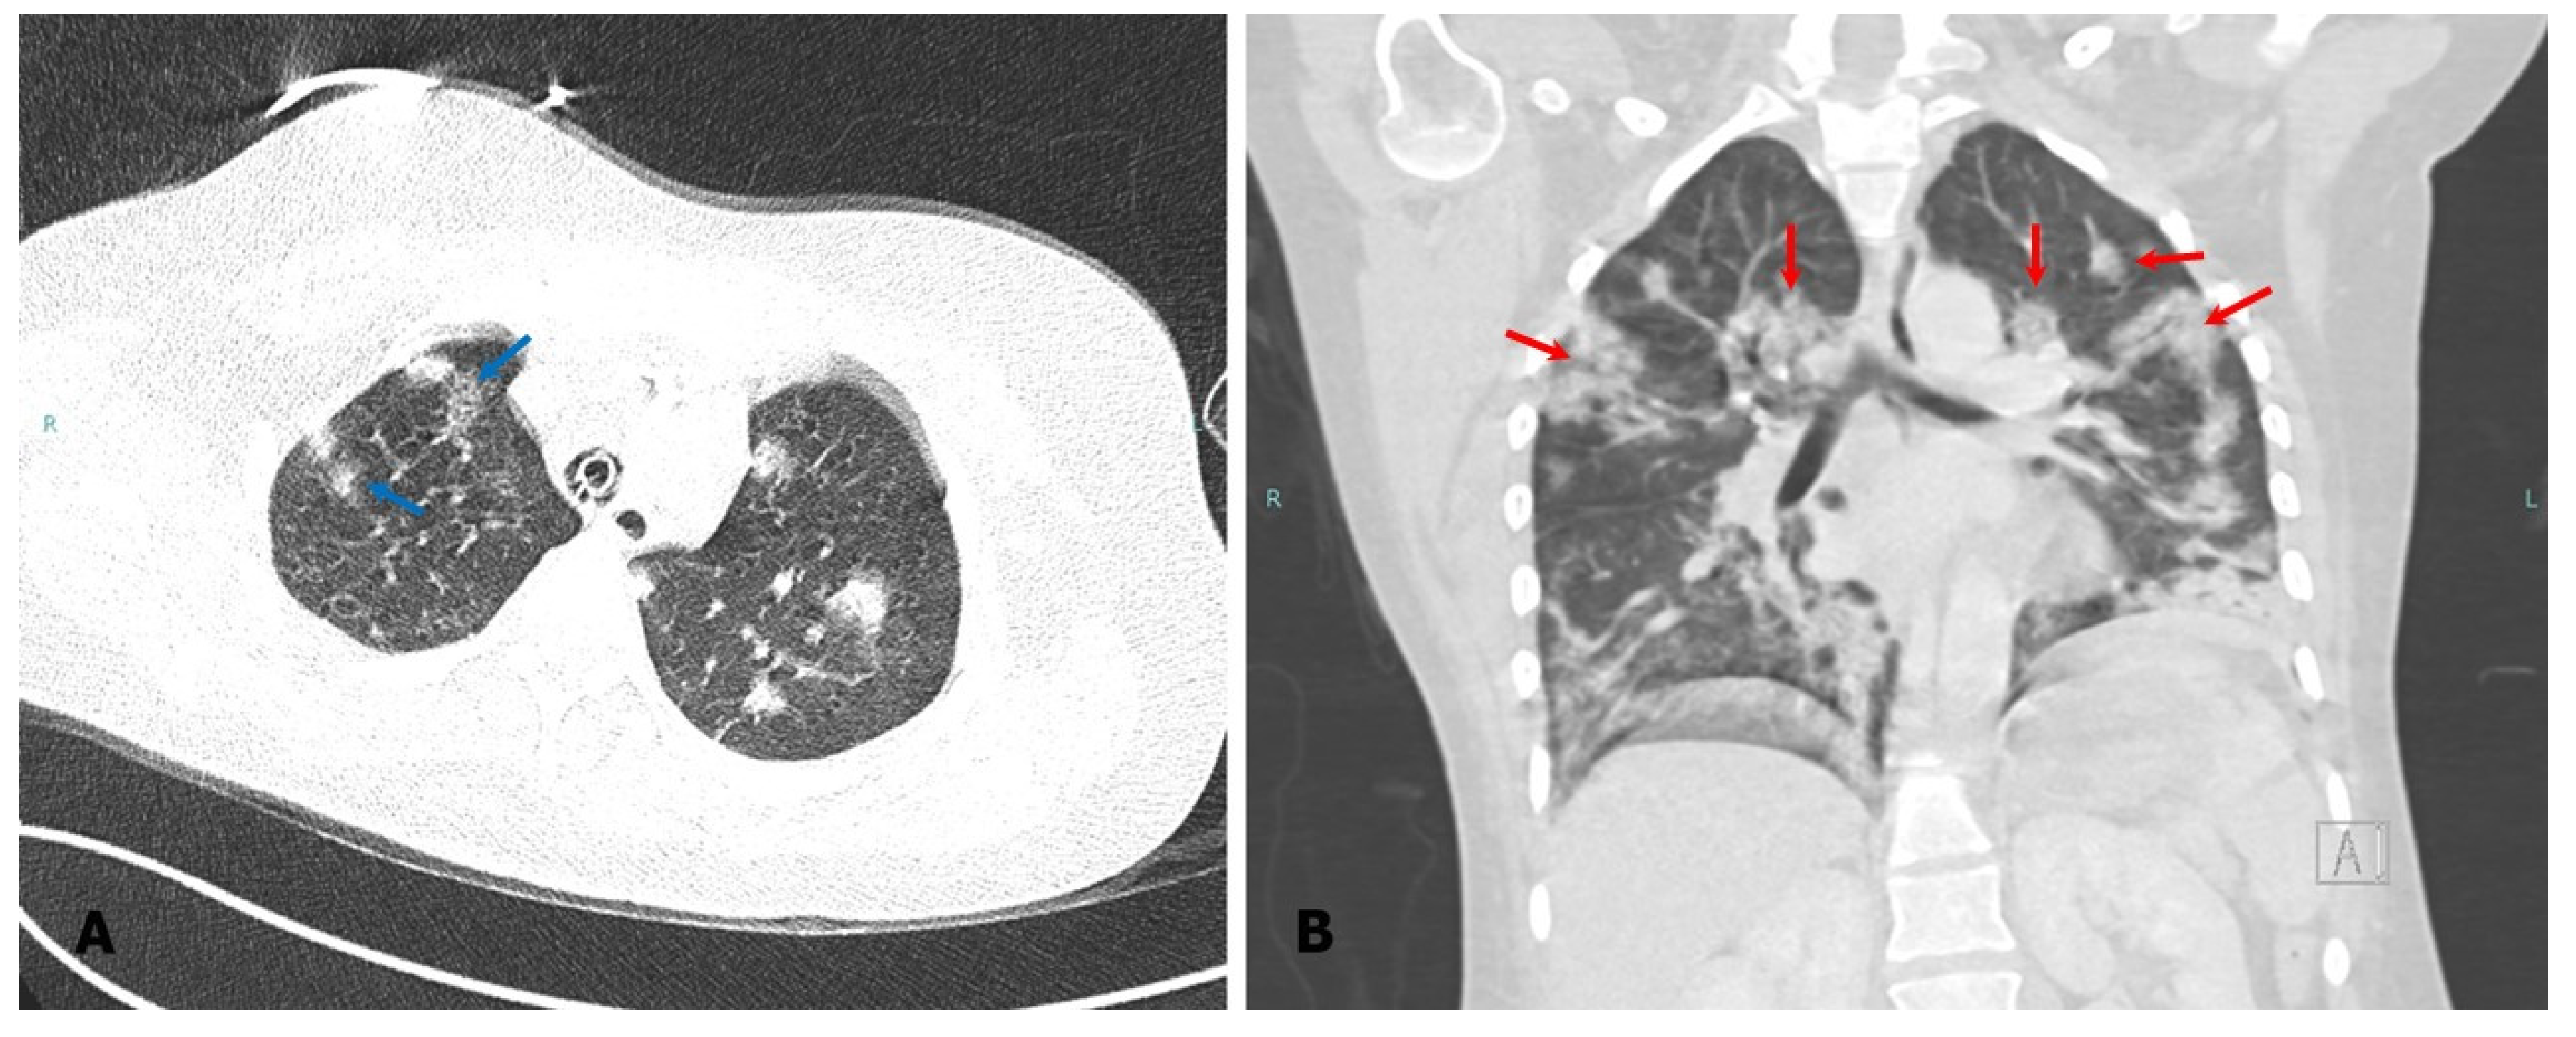

Case Presentation